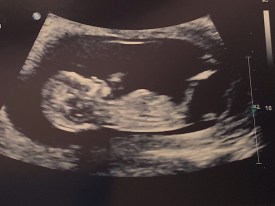

Things like that…so it’s a mixed bag of fun. Yes…there are some things that are amazing…here’s a progression of photos:

And I admit…I do love going to ultrasounds because it’s really fun watching her do her baby thing. She’s very animated…she’s always moving, turning, standing on her head…totally normal 🙂 I think.